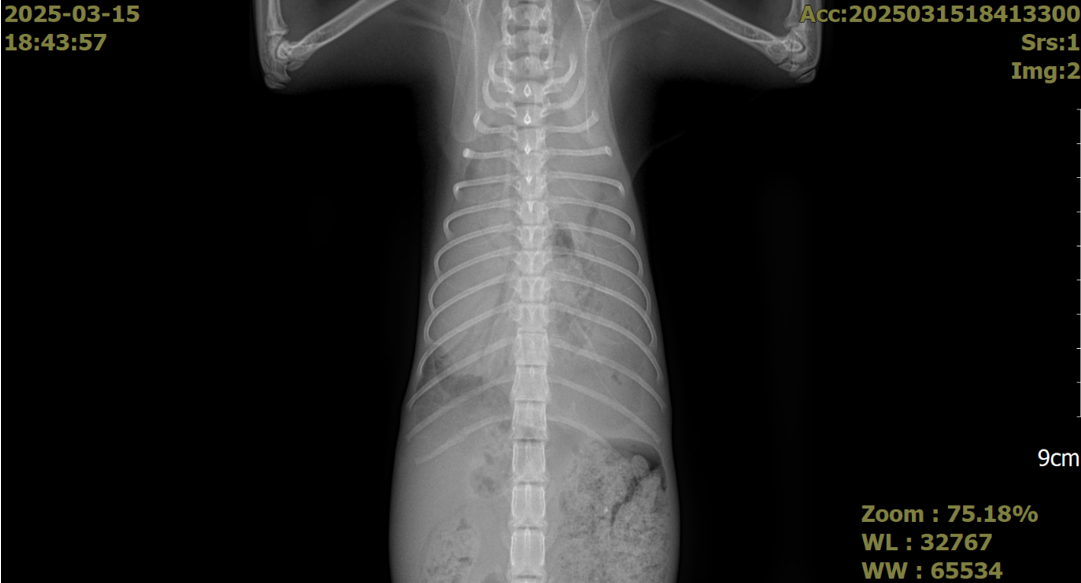

흉부 및 복부 X-ray를 촬영한 결과 흉수 및 복수가 모두 확인되었으며 심장 주변에 복강 장기들이 들어차면서 폐가 허탈되어 있는 모습을 확인할 수 있었습니다.

특히 폐 음영이 정상적으로 나타나는 부위가 없어, 호흡 곤란의 원인을 쉽게 확인할 수 있었습니다.